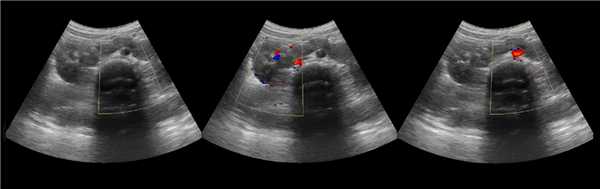

В нормальной почке пирамиды гипоэхогенные, корковое вещество и колонны Бертини изоэхогенны друг другу. В синусе располагается в норме невидимый ЧЛК, гиперэхогенная соединительная и жировая ткань, гипоэхогенные сосуды и вершины пирамид.

Бывает колонна Бертини врезается в центральную часть почки, разделяя ее полно или неполно на две части. Такая паренхиматозная перемычка — это паренхима полюса одной из эмбриональных долек, которые сливаясь образуют почку; состоит из коры, пирамид, колонн Бертини — все элементы без признаков гипертрофии или дисплазии. Термин гипертрофия колонны Бертини не отражает морфологию структуры, точнее считать данное образование паренхиматозной перемычкой.

Рисунок. На УЗИ округлое образование разделяет почечный синус на два сегмента с общей лоханкой; междолевые артерии огибают образование; эхогенность и интенсивность сосудистого рисунка внутри близка корковой зоне. Заключение: Гипертрофия колонны Бертини или неполная паренхиматозная перемычка. Это вариант нормального строения почки. Термин «неполное удвоение ЧЛК» неверный, т.к. неполная паренхиматозная перемычка не является признаком удвоения ЧЛК.

Рисунок. На УЗИ синус почки разделяет полная паренхиматозная перемычка (1, 2). В таких случаях разграничить удвоение почки от гипертрофии колонны Бертини поможет экскреторная урография. Удвоенная почка покрыта общей фиброзной капсулой. Полное удвоение предполагает наличие двух лоханок, двух мочеточников и двух сосудистых пучков. Неполноудвоенная почка (3) питается одним сосудистым пучком, мочеточник может быть удвоен вверху и впадать в мочевой пузырь одним или двумя устьями. Удвоение ЧЛК и мочеточников — фактор риска развития патологии (пиелонефрита, гидронефроза и др.).

Рисунок. На УЗИ синус почек широкий, неоднородной эхоструктуры (1, 2). На фоне гиперэхогенного жира гипоэхогенный очаг округлой формы (2), при ЦДК междолевые сосуды проходят через гипоэхогенную зону без смещения (3) — это гипоэхогенный жир. При ожирении липоматоз синуса можно ошибочно принять за атрофию паренхимы.